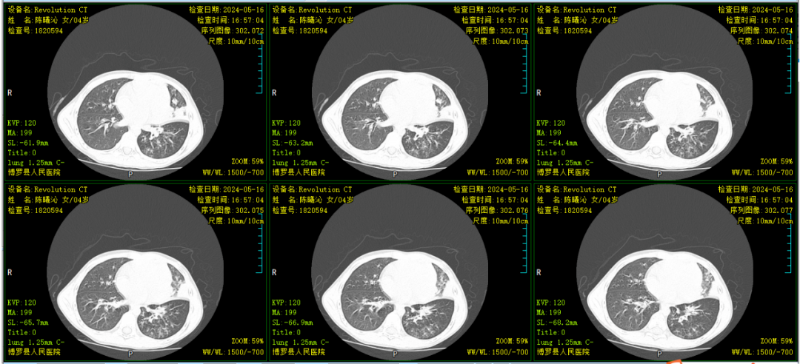

文章配圖

△完善胸部CT示:雙肺炎癥。

患兒肺部局部實變明顯,予行支氣管肺泡灌洗治療。肺泡灌洗液送檢提示肺炎支原體感染及鼻病毒感染,予加用阿奇霉素抗感染治療。行電子支氣管鏡肺泡灌洗治療9天后,患兒無咳嗽,肺部聽診無啰音,復查胸部CT示:對比原片,原雙肺病灶基本吸收。病情痊愈出院。